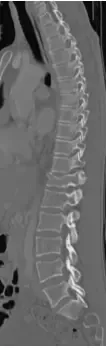

48 yo Female had a sledding injury when she landed on her buttocks following a fall. She felt a “pop” and immediate back pain. She was able to walk briefly, but quickly incapacitated by pain. Her examination suggested an injury to the lower thoracic spine. She was neurologically intact. She had uncontrolled pain. X Rays and CT scan of the patient showed fracture of T12 vertebral body.